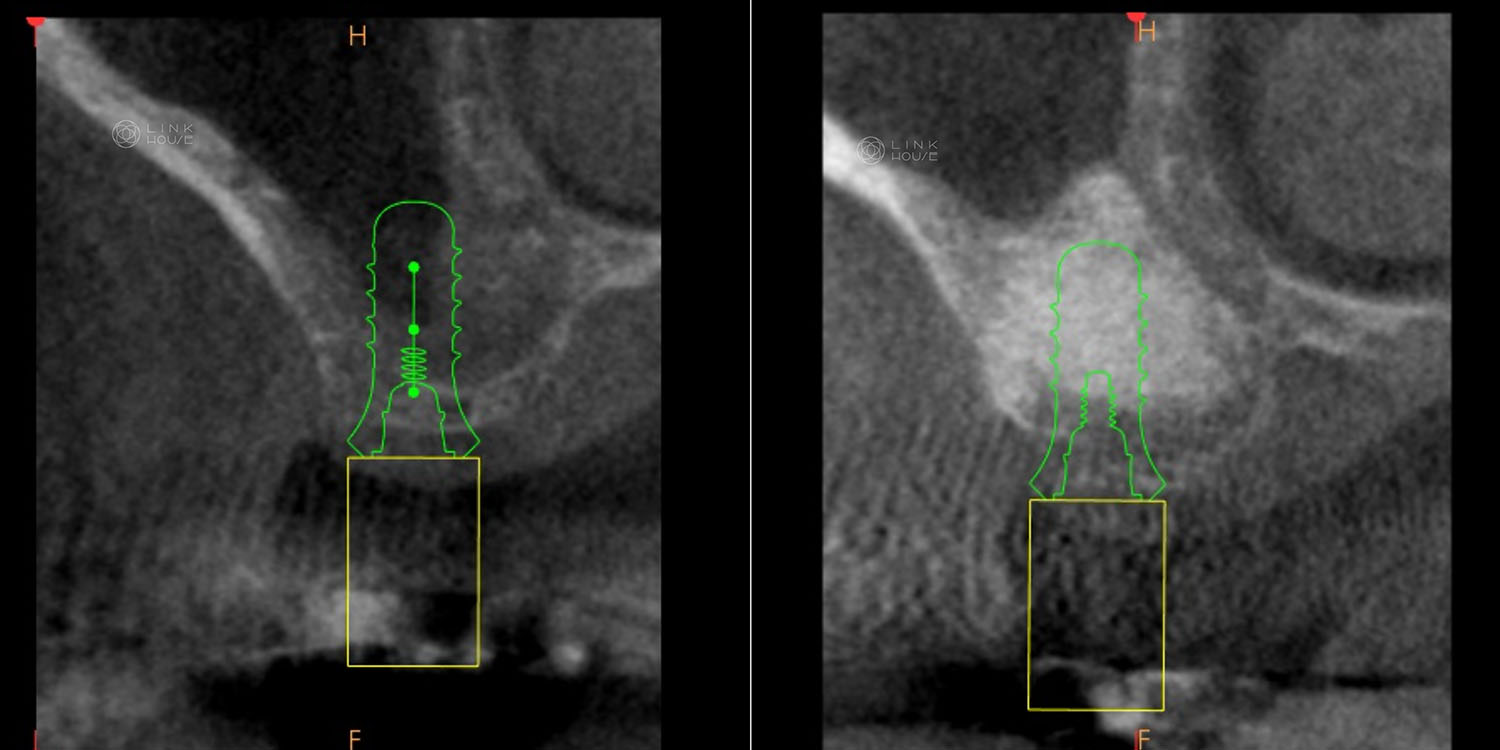

The area is typically assessed using a 3D CBCT scan, which offers a highly accurate view of the jawbone and sinuses. Based on the scan results, a suitable treatment approach—whether straightforward or more complex—can be chosen. Modern technology allows the procedure to be meticulously planned and simulated on a screen, helping to make the actual treatment quicker and safer.